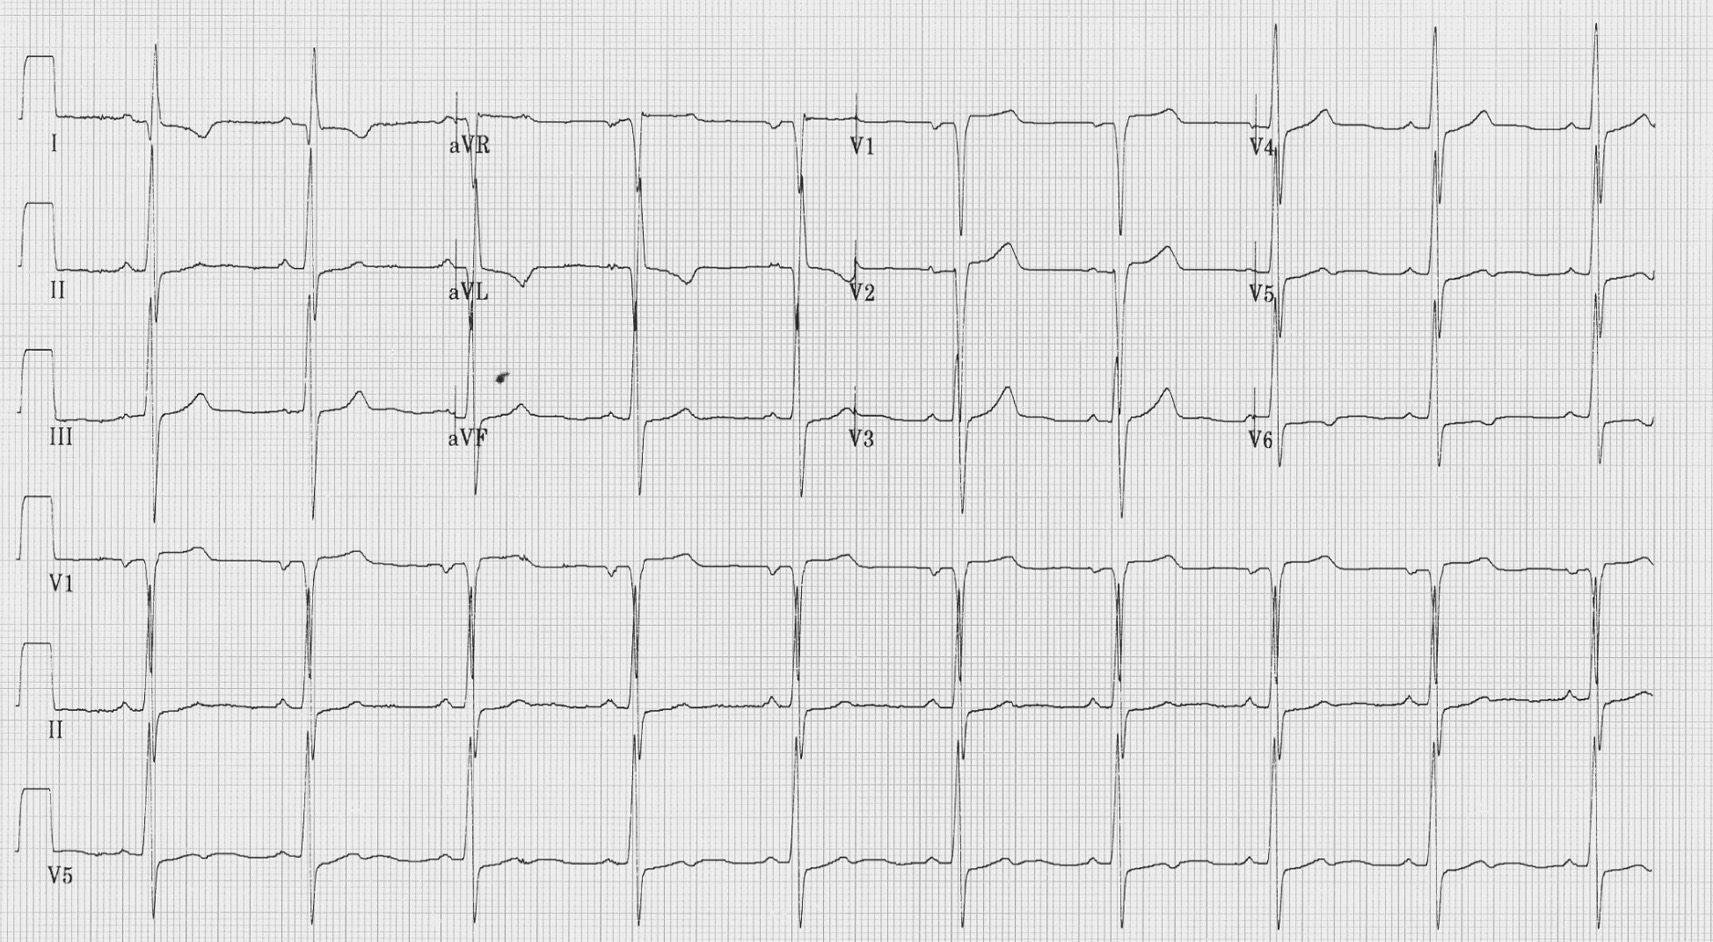

Figure 4 : ECG pendant une embolie pulmonaire, déviation axiale droite, S1Q3T3, fibrillation atriale